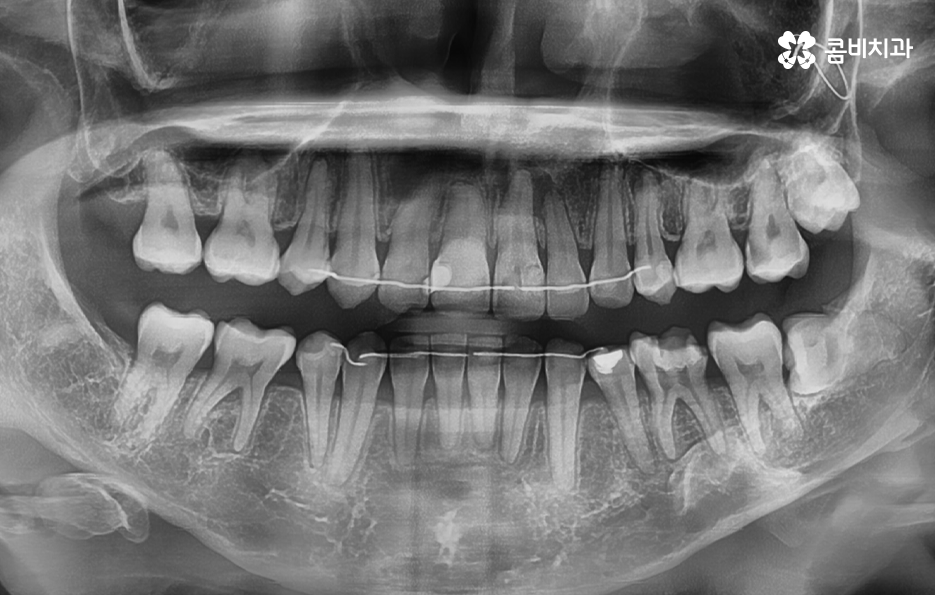

사랑니는 치아 중에서도 가장 마지막에 맹출이 되며 현대인들은 턱뼈가 좁아지는 추세이기 때문에 마지막에 자라는 사랑니는 위 케이스처럼 윗니의 경우 어금니의 높이 보다 다소 낮게 자라는 경우가 많고 아랫니의 경우 매복되어 있거나 누워서 자라는 사랑니의 형태로 자라는 경우가 많이 있는데요. 이러한 사랑니의 형태로 인해 어금니와 사랑니 사이에 이물질이 끼기 쉽고 칫솔질이 잘 닿지 않기 때문에 충치 뿐 아니라 잇몸 염증이 발생되는 경우가 많으며 사랑니 어금니 통증의 원인이 주변의 세균 증가로 인해 충치로 이가 썩은 경우부터 잇몸이 자주 붓고 염증이 심해지면서 통증을 느끼는 경우가 40,50대 이후에 흔하게 발생되는 사랑니와 인접한 어금니의 문제로 볼 수 있어요

일반적으로 30대 이후에는 치주질환이 급증하게 되는데 40,50대 이후에는 잇몸이 점점 내려 앉게 되고 부분적으로 맹출된 사랑니 주변 잇몸 역시도 조금씩 내려앉는 경우가 많이 있는데요. 사랑니 사진을 보시면 아시겠지만 일반적인 치아의 높낮이와는 달리 사랑니가 어금니의 뿌리 부분 정도 높이에 자리하고 있는 것을 볼 수 있어요.